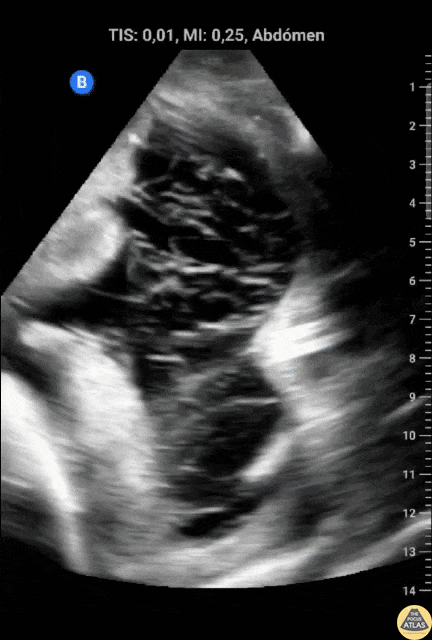

Bowel-GI - Ascites With Spider Web Sign

A 19 year old male, with hx of cocaine abuse presented to the ICU for respiratory insufficiency due to cardiogenic pulmonary edema. POCUS evaluation of the abdomen demonstrated ascites with Spider Web Sign, which is not expected in cardiogenic ascites. Because of this, peritoneal tuberculosis was suspected. It was later discovered that the patient had close contact with a person who was being treated for a confirmed tuberculosis diagnosis. Contributor: Dr. Alessandro Ferreira Hospital Metropolitano de Alagoas